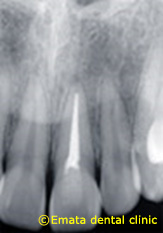

患者さんは14歳の中学生女の子です。当院のホームページを見て宇都宮の東方から時間をかけてお母さんと一緒に来院されました。前歯を数年前に神経をとってしまったので向かって右の前歯が変色してます。年齢的に前歯は気になりはじめますよね。ラミネートも綺麗にしあがりますが、20歳前は出来るだけ前歯は被せないほうがよいですよ。

レントゲン像 向かって右の白い部分は神経をとってしっまたからです。

歯はまったく削ってません。